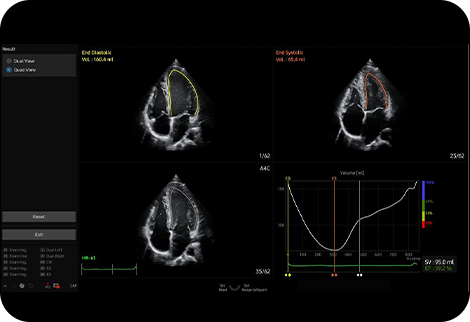

Měření ejekční frakce levé komory |

AutoEF je funkce, která pohodlně měří a kvantifikuje ejekční frakci. Výběrem tří bodů levé komory se vypočítá objem na konci systoly a na konci diastoly, což napomáhá rychlému a efektivnímu posouzení funkce srdce.

![]()